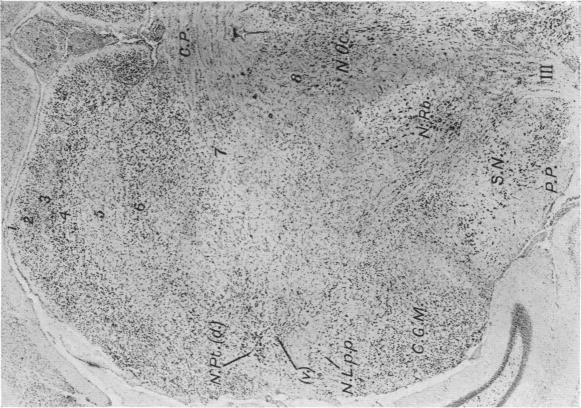

The Thalamus of Tupaia minor.

J Anat. 1929 Jan;63(Pt 2):177-206.5.